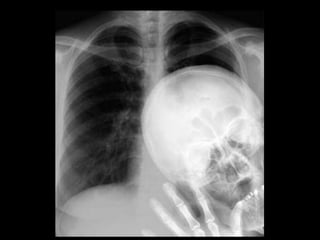

This document provides an overview of normal musculoskeletal imaging. It discusses basic x-ray concepts and densities. It then reviews normal anatomy as seen on x-rays of the skull, spine, pelvis, chest, and extremities. Key anatomical structures are labeled on example x-rays for the shoulder, hip, knee, and foot. Quizzes are included to test recognition of anatomical structures and patient age based on x-rays.